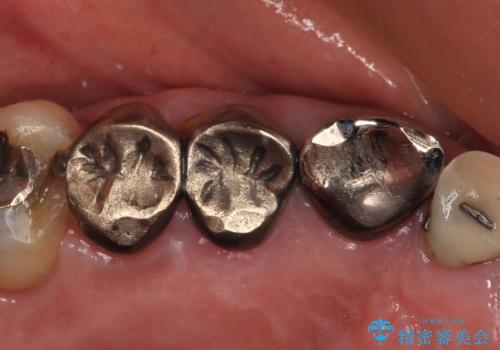

破折した歯 オールセラミックブリッジの補綴治療

- 歯が割れてしまったとのことで来院された患者様です。

痛みは特にありませんでしたが、以前から歯が割れていることを指摘されており、徐々に不快感が増してきたとのことでした。

咬合力が強く、抜歯となる破折歯の前後の歯はいずれも神経が除去された歯であることから、ブリッジでは長期的な予後に不安があると判断されましたが、前後の銀歯も一気にきれいにしたいとのことで、オールセラミックブリッジによる補綴治療を行うこととしました。